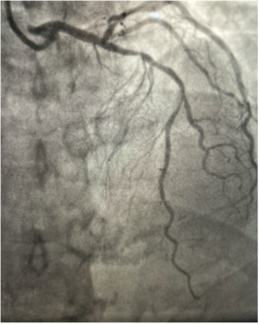

A difficult-to-cross coronary lesion, due to vessel tortuosity and almost complete occlusion, was crossed using the wire surfing technique. This case report captures the details of the case and presents it in the light of fluid hemodynamics,...